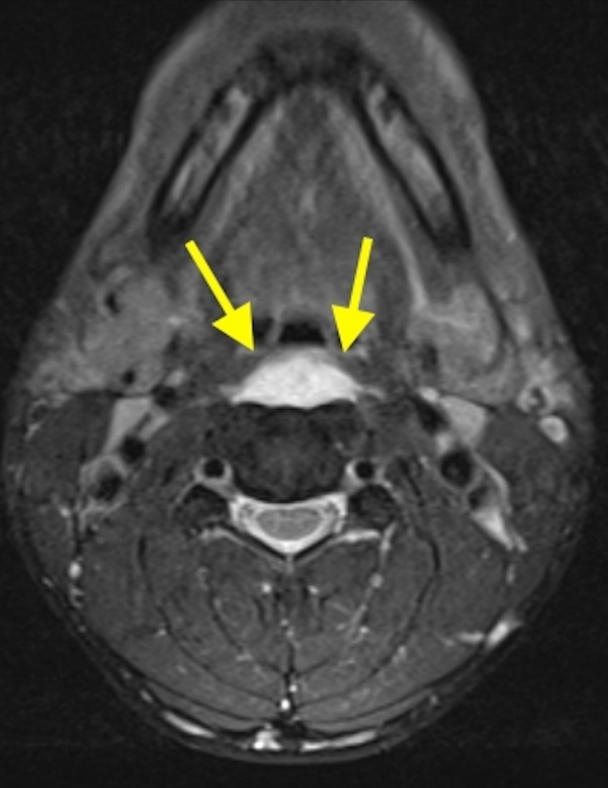

典型病例介绍

36岁女性,急性颈痛、吞咽困难伴颈部僵硬,MRI示C1-2前部颈长肌增厚呈低信号,提示钙化(长箭头)和C1-4椎前积液(无线箭头),经类固醇和止痛药治疗8天后症状消失,复查MRI提示上述表现消失。(PMID: 18765656)

C1-2前侧低信号(无线箭头)和C1-5椎前水肿(长箭头) (PMID: 19567634)